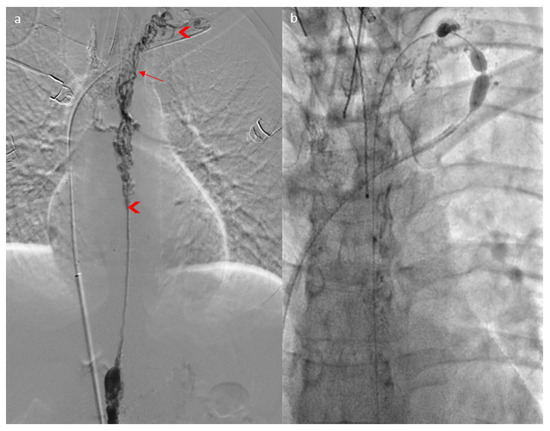

2. Case Report

3.1. Case Discussion and Physiopathological Hypothesis